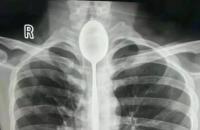

शख्स को है ये दुर्लभ बीमारी

डॉक्टरों की मानें तो शख्स को हीमोलैक्रिया (haemolacria) नाम की एक अजीब बीमारी है। यह एक दुर्लभ बीमारी है जो खून को आंसुओं में मिक्स कर देती है, जो बाद में आंख के रास्ते बाहर आता है। इस बारे में अभी कोई आंकड़े नहीं है कि इस बीमारी से दुनियाभर में कितने लोग पीड़ित हैं। उन्होंने कहा कि हीमोलैक्रिया होने के कई कारण हो सकते हैं, जैसे- आंखों में इन्फेक्शन, चेहरे की चोट या सूजन और आंख के अंदर ट्यूमर का होना।